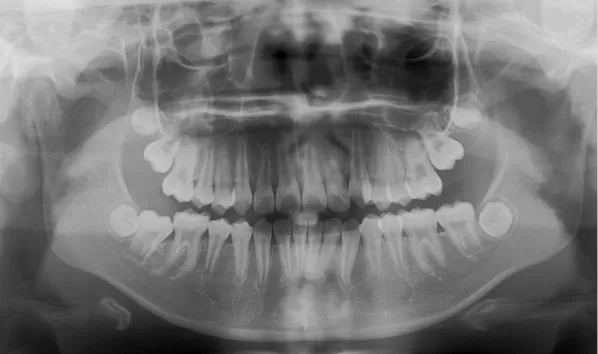

Rayons X avant le traitement

[Radiographie panoramique/Céphalogramme latéral]